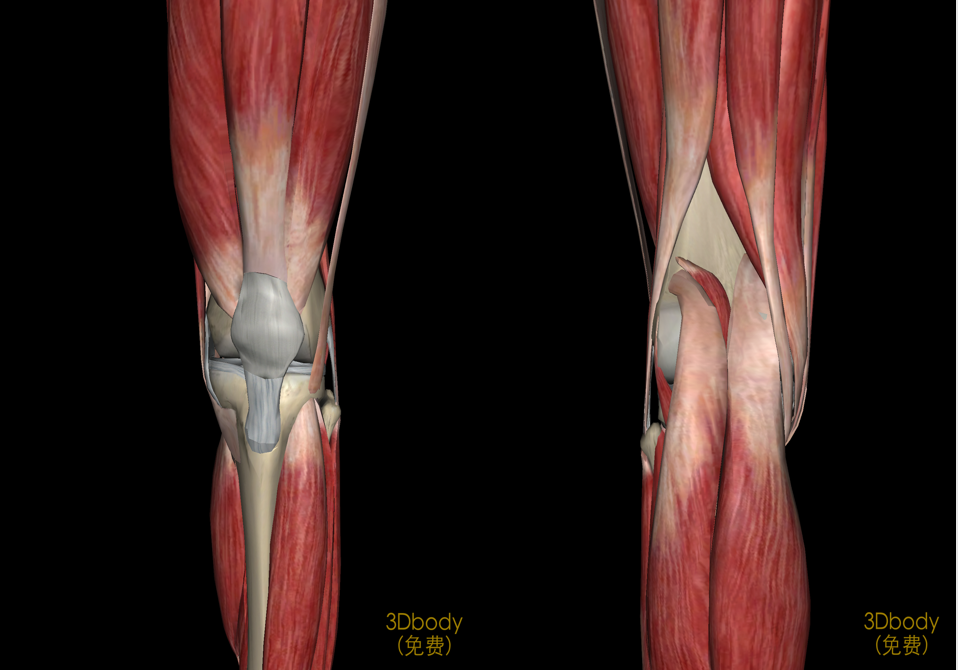

膝关节解剖

病因和发病机制关节的基本结构:关节面、关节软骨、关节腔、关节囊关节软骨:厚度约为2-7mm软骨表面光滑,摩擦系数很小,故有利于关节活动。

病理滑膜的各种炎性反应、增生和表面渗出。关节囊的增厚和粘连。关节软骨的软化、撕裂、磨损。骨赘形成。